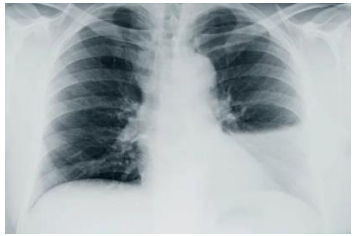

Analise a telerradiografia a seguir.

A telerradiografia de tórax acima é de um paciente do sexo masculino, diabético controlado, 45 anos de idade, que estava há uma semana com tosse produtiva, febre 39ºC, dor torácica à esquerda. Exames de sangue com os seguintes resultados: hemograma exibindo 14.480 leucócitos/mm3 , proteína C reativa 9,8mg/L, velocidade de hemossedimentação 80 mm/h, glicose 150mg/dL, lactato desidrogenase sérico 1.280 U/L, proteínas totais 14g/dL, ureia e creatinina normais.

O líquido pleural foi coletado e análise laboratorial revelou: líquido turvo, adenosina deaminase negativo, incontáveis polimorfonucleares, alguns mononucleares, proteína 9g/dL, glicose 40mg/dL, lactato desidrogenase 900 U/L.

Com base nessas informações, assinale a opção que melhor responde, respectivamente, às seguintes questões: o líquido pleural do paciente se caracteriza como exudato ou transudato? Qual o diagnóstico mais plausível e razoável? Como tratar?